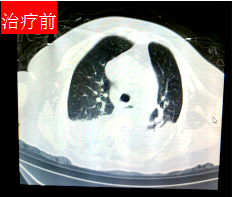

(治疗前后胸部CT对比)